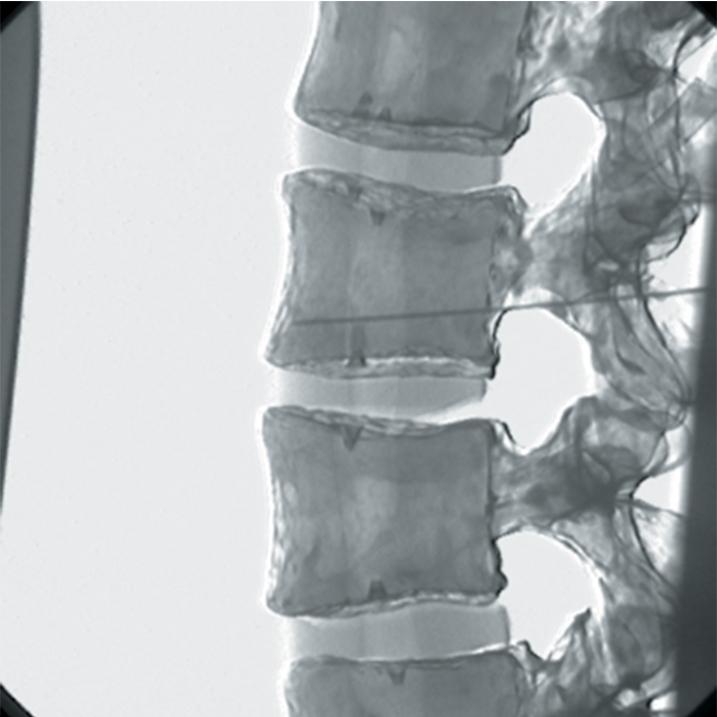

The Regional Anaesthesia Simulation Manikin has been designed by a Consultant Anaesthetist at the Manchester and Salford Pain Centre for training anaesthetists in correct needle placement in Nerve Blocks for pain management.

- Orientation of image and identification of appropriate radiographic landmarks

- The end point of simulation is the correct radiographic appearance

- Epidural injections at all spinal levels

- Lumbar facet joint injection and radio frequency denervation of posterior primary ramus

- The manikin consists of a specially coated plastic human skeleton, head covered in artificial skin and fabric covered torso, on which trainees can practice the placement of needles under X-ray image intensifier control

- The X-ray density of the manikin is low so that the doses of radiation used during simulated procedures are reduced